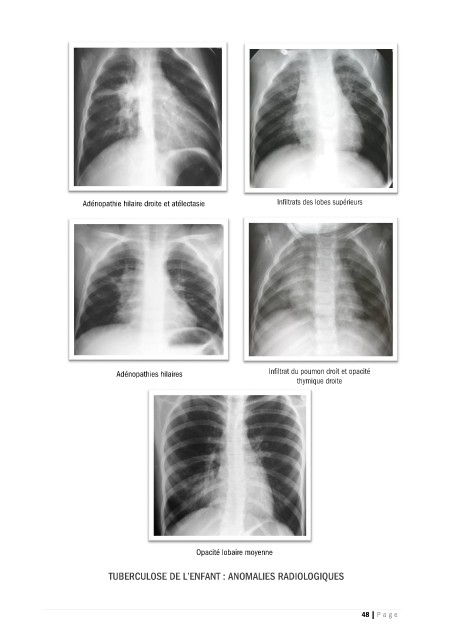

Adénopathie hilaire droite et atélectasie          Infiltrats des lobes supérieurs

Adénopathies hilaires                   Infiltrat du poumon droit et opacité

thymique droite

Opacité lobaire moyenne

TUBERCULOSE DE L’ENFANT : ANOMALIES RADIOLOGIQUES